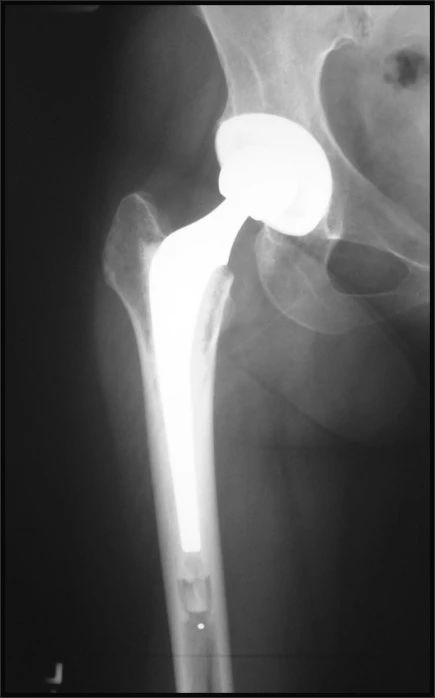

现代骨水泥型假体的设计要素:

水泥柄的争论:

高抛光骨水泥柄

- 高抛光表面工艺

- 无颈领设计

- 锥形直柄的假体形态

- 钴铬钼合金材质

设计理念:假体“有限下沉”理论

高抛光的表面使得假体与骨水泥床之间的磨损最小化,并允许假体有限的下沉,结合中置作用将轴向应力转化为对骨水泥床的横向压力。

CPT 高抛光水泥柄:因此,采用表面抛光的骨水泥型假体柄又重新成为大部分医生的选择。